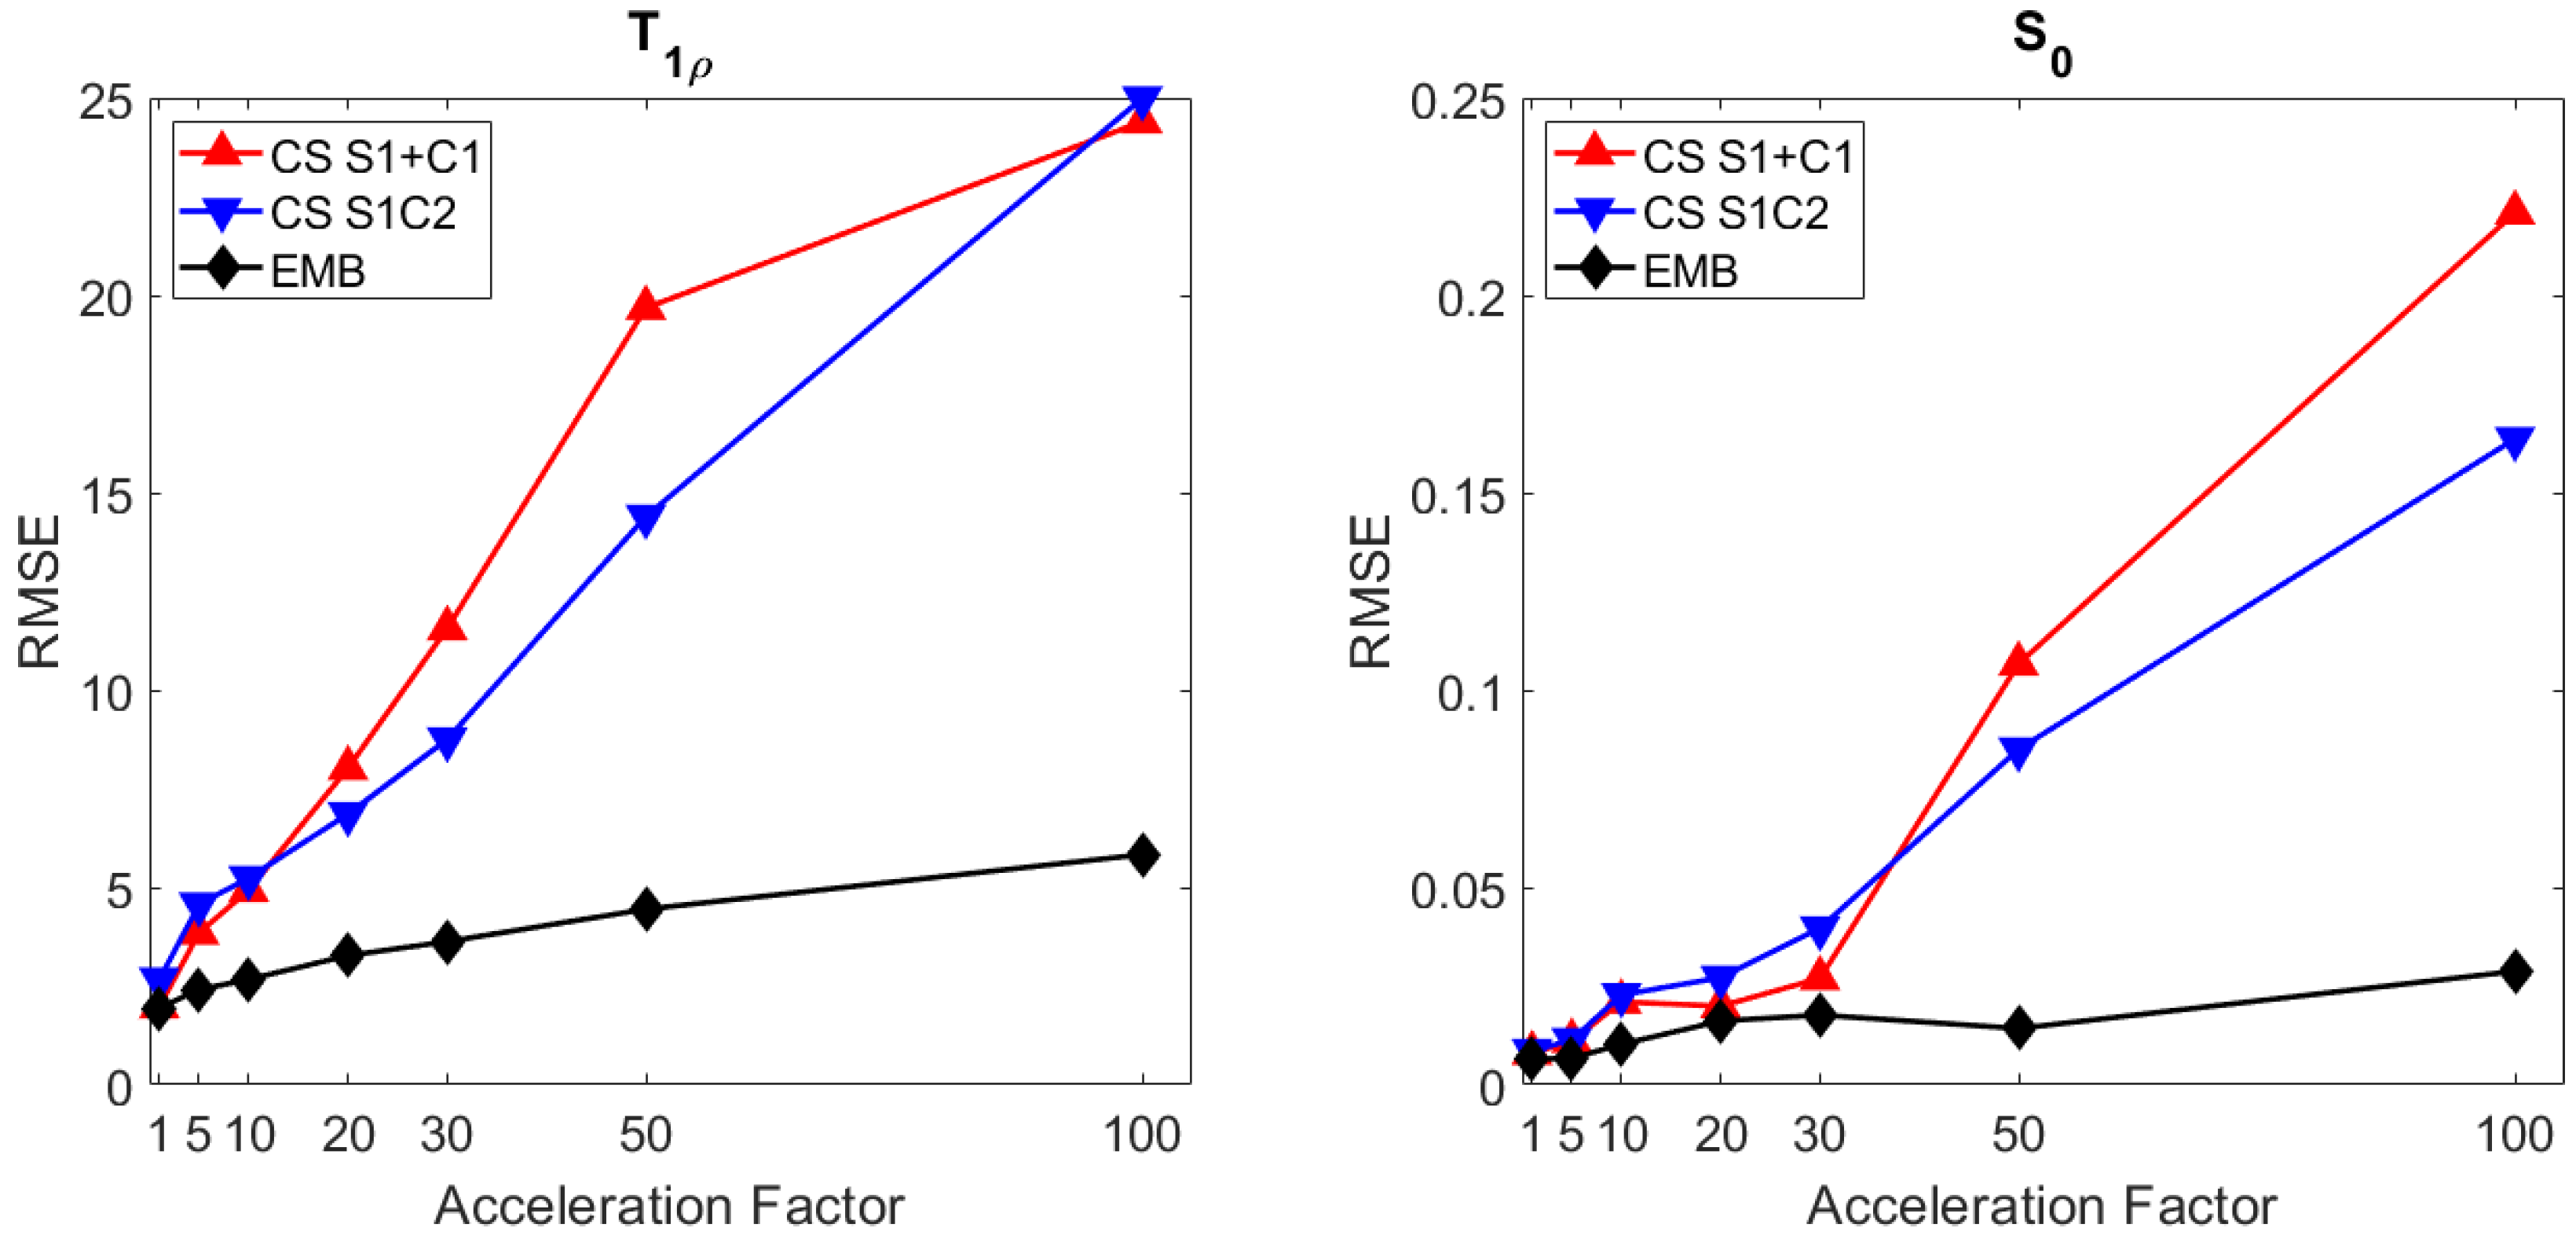

4.1. Simulated Golden Angle Radial Data